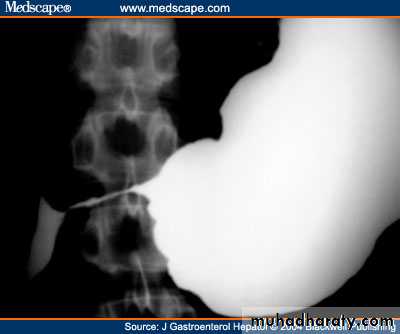

A long history of peptic ulcer disease. The pain may become unremitting. The vomitus is totally lacking of bile. Very often it is possible to recognise foodstuff taken several days previously. The patient commonly complains of losing weight, and appears unwell and dehydrated.O/E: It may be possible to see the distended stomach and a succussion splash may be audible.

Investigation of the patient with endoscopy and contrast radiology with biopsy of the area around the pylorus is essential to exclude malignancy.